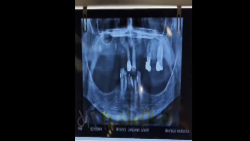

جایگزینی ایمپلنت دندان